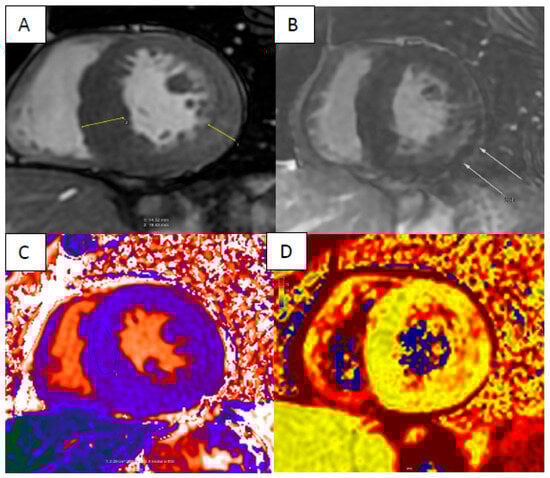

5. Anderson–Fabry Disease